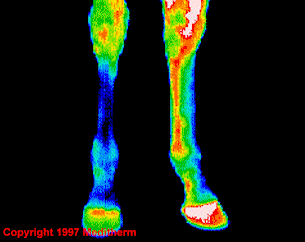

Termograma in infrarosu

Proces inflamator picior stanga spate